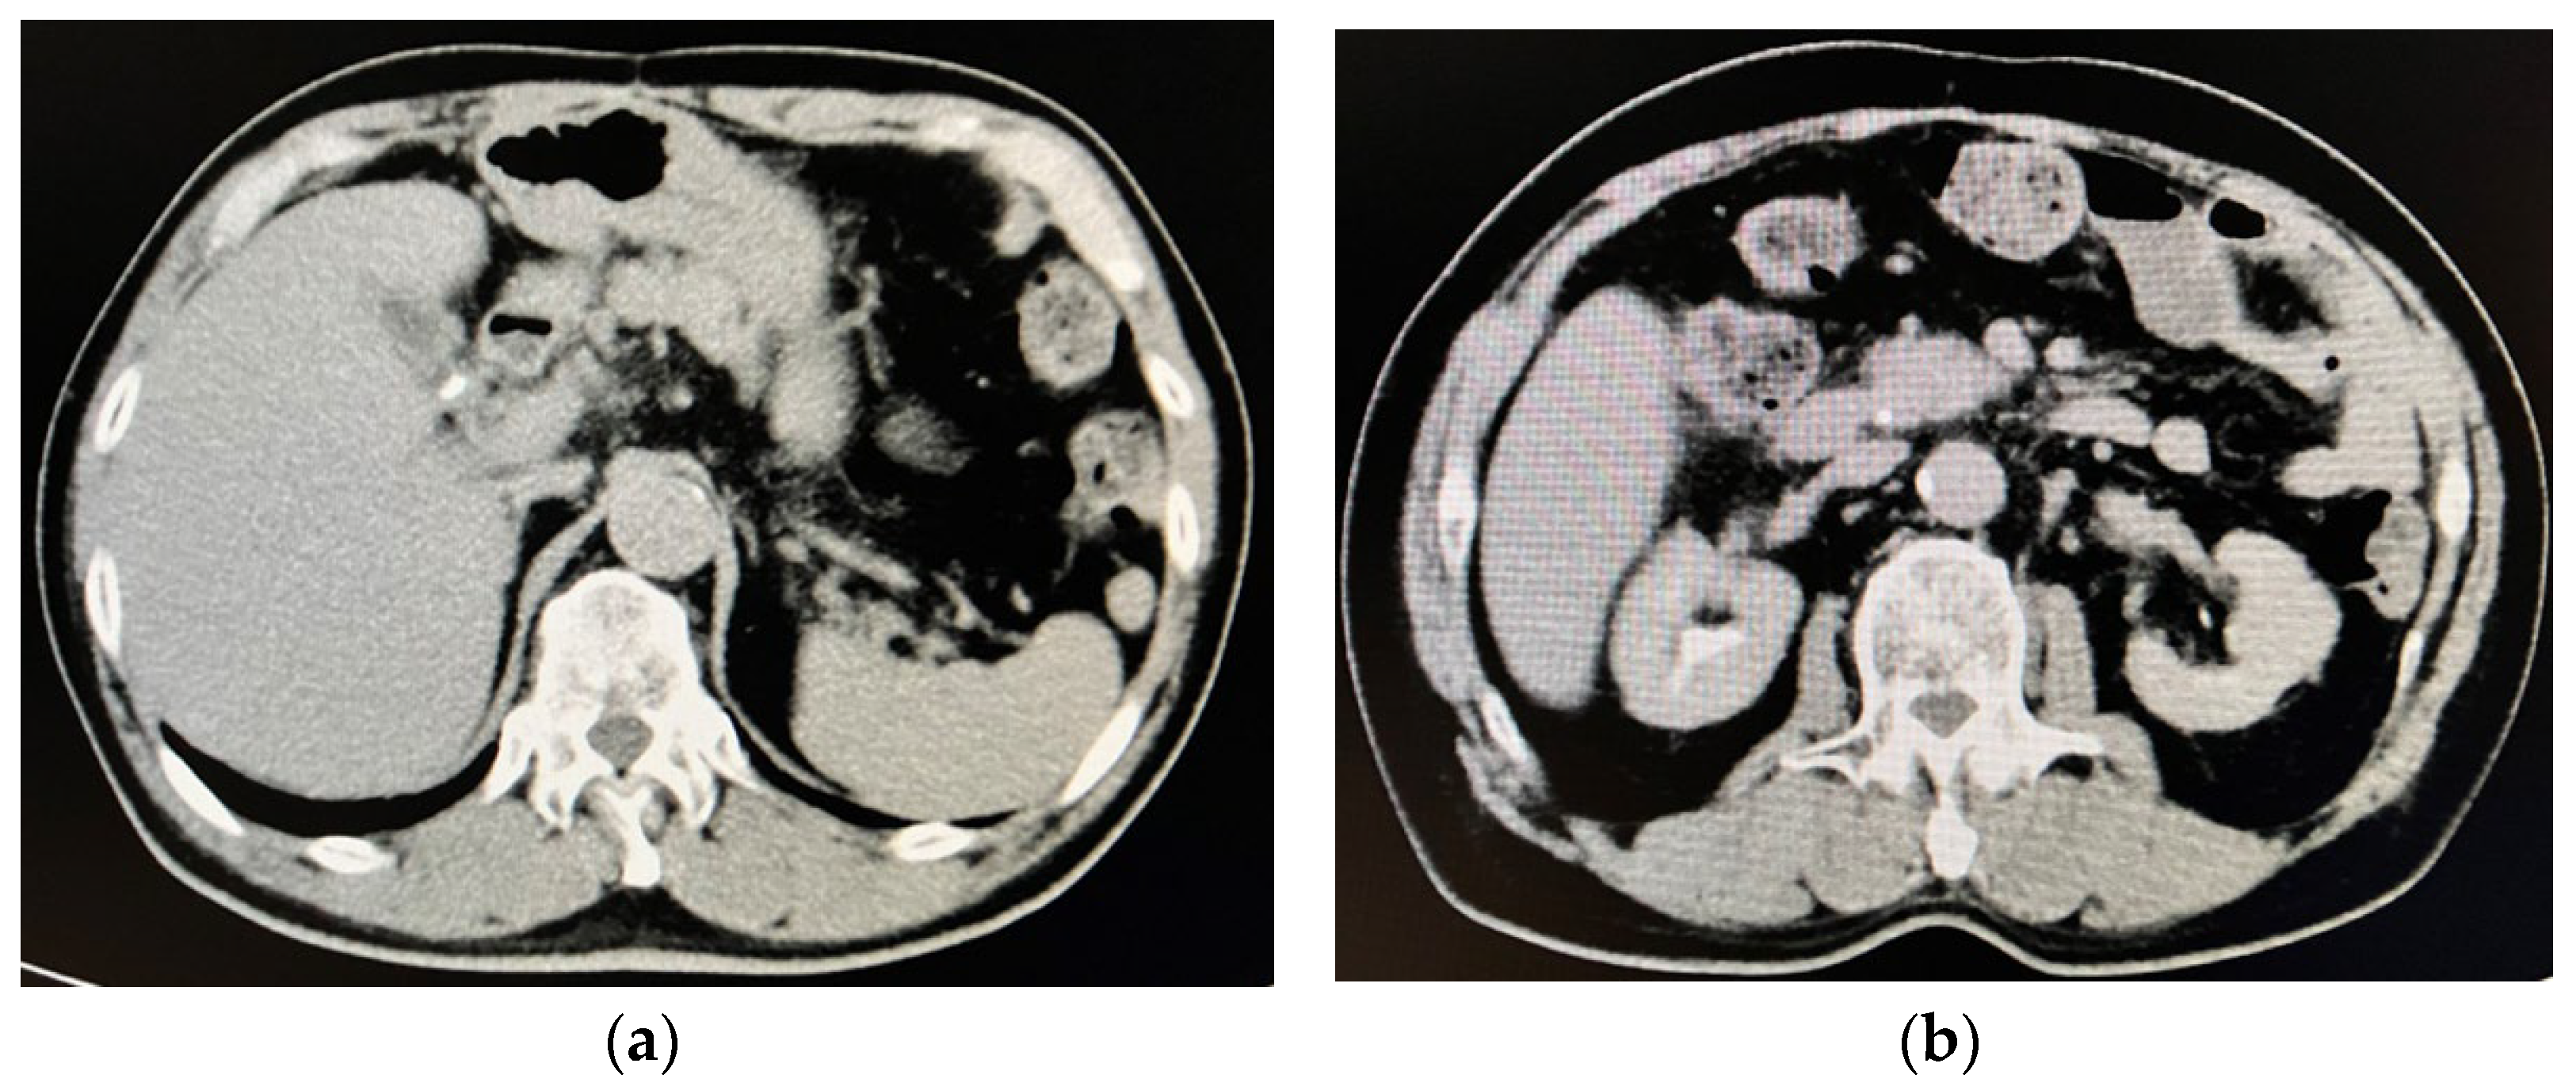

2. Case Presentation